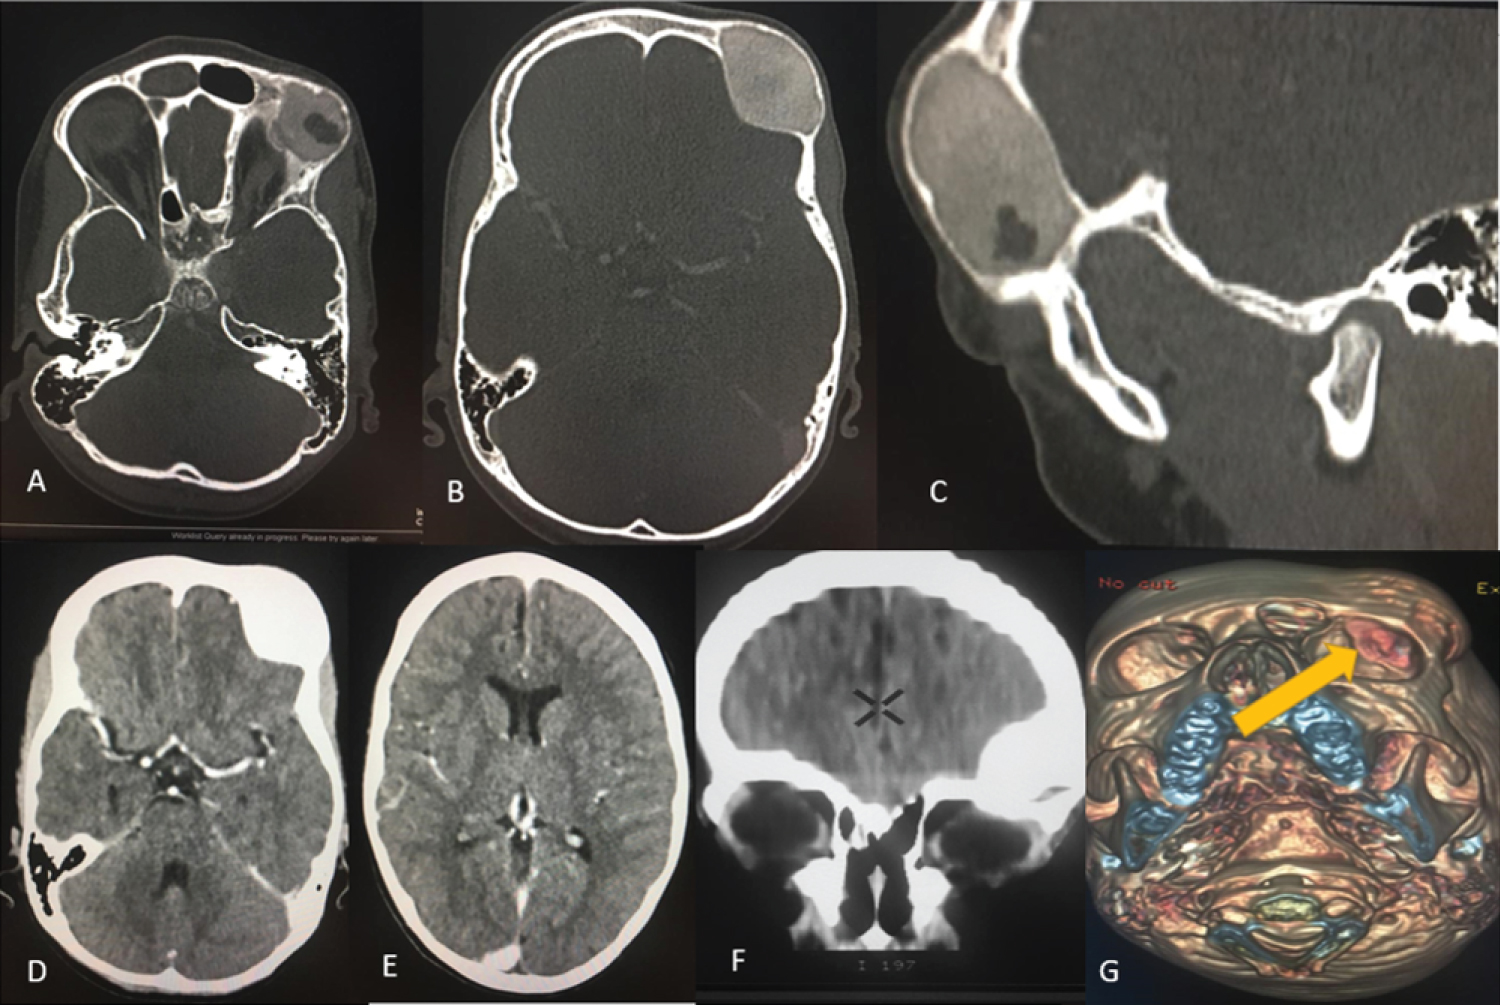

Contrasted computed tomography (CT) scan of the brain demonstrated a well-defined, expansile, oval shaped, intramedullary non-enhancing osseous lesion in the left frontal bone measured 3.9 × 2.6 × 4.0 cm. There was small intra-lesional lytic area. There was thinning of the inner plate of the cortical bone. The lesion abuts upon the orbital roof. There was no periosteal reaction. There was no intra-cranial extension. The overlying soft tissues were normal. There was no intra-conal extension. Both orbits were normal. The cerebrum, cerebellum, midbrain, pons and medulla were normal. No satellite lesions noted in the head and the demonstrated upper cervical vertebrae (Figure 1).

Figure 1: (A,B) Contrasted CT axial; (C) (Sagittal) on bone window; (D,E) (Axial); (F) Coronal reformat on soft tissue window; (G) 3D bone reconstruction. (A) (Lower cut); (B) (Upper cut); (C) Demonstrated an expansile, oval shaped intramedullary non-enhancing osseous lesion in the left frontal bone with a small area hypodensity and inner table thinning; (D,E and F) Demonstrated a well-defined osseous lesion with no intracranial extension, no obvious mass effect to the brain or intracranial lesion; (G) Demonstrated protuberant bony lesion that abuts upon the orbital roof the left eye. View Figure 1